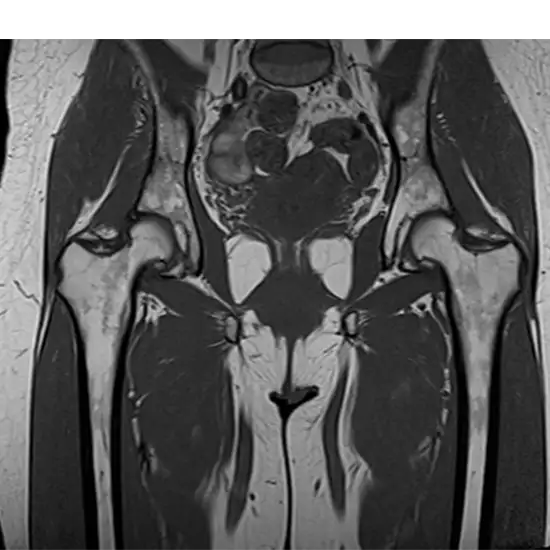

What is MRI Screening of the Hip Joint?

An MRI of the hip can tell you right away what's wrong, such as bursitis, strained or overworked hip muscles, joint pain, wear and tear on the head of the hip joint, and other movement restrictions. In these pictures, the doctor can see the hip joint, wear and tear (arthrosis), and other bone problems.

MRI (Magnetic Resonance Imaging) screening of the Hip Joint is a non-invasive radiology test used to evaluate the condition of the Hip Joint and surrounding tissue. MRI Screening Of the Hip Joint is done to look for Hip Joint conditions and the surrounding area.